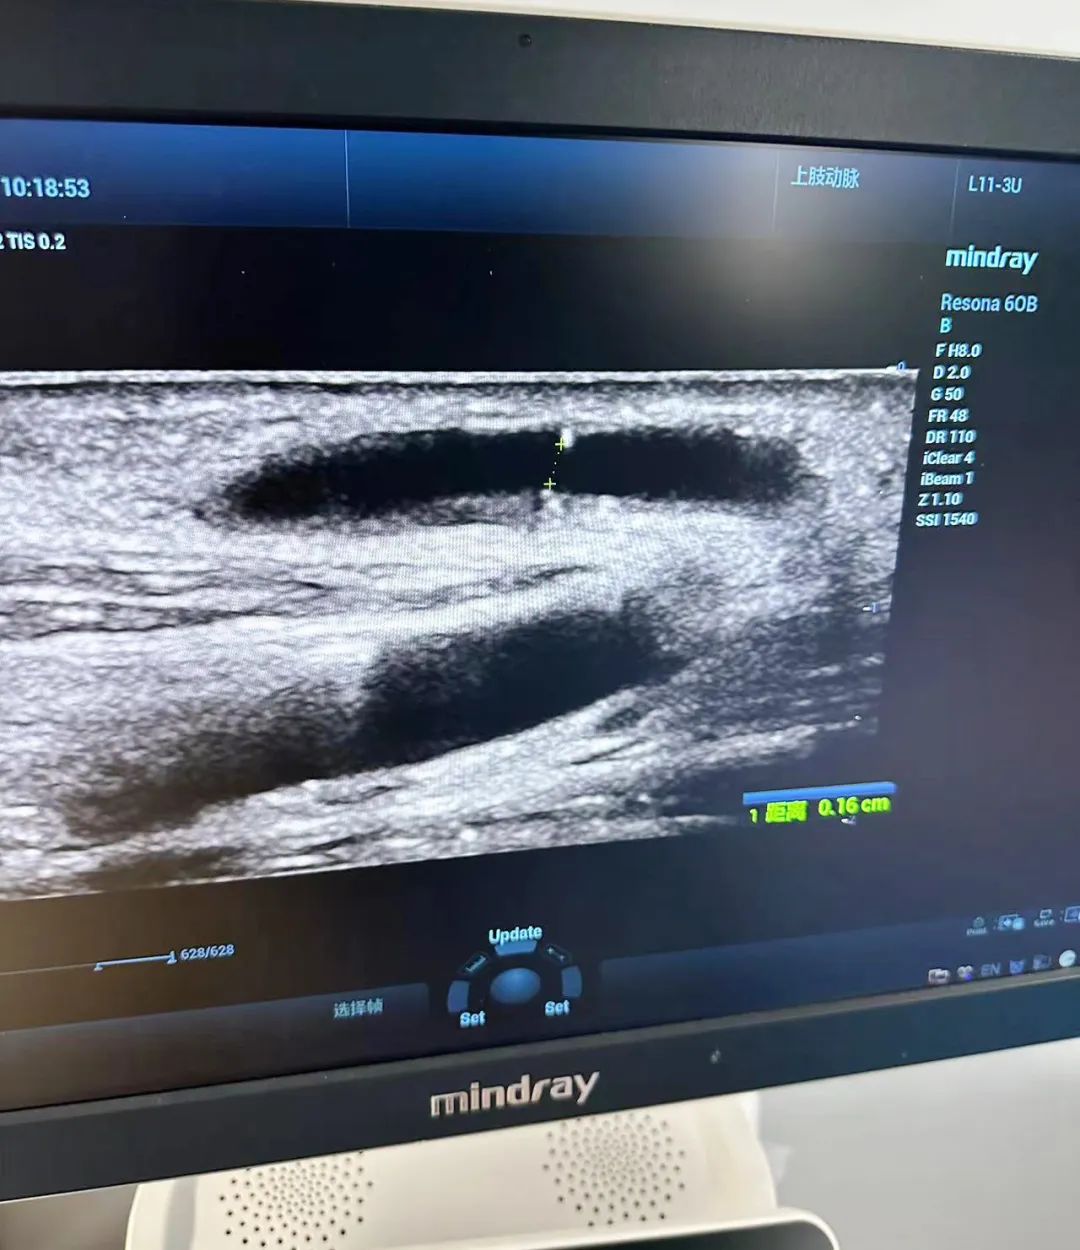

12日上午,在我院四樓遠(yuǎn)程會診中心,李月紅教授與血透中心醫(yī)護(hù)人員共同開展一場腎友交流會活動。通過與腎病患者面對面的交流,她們更深入地了解了患者的實(shí)際需求和困擾,并就血管通路、腎性貧血、高磷血癥、血液灌流、飲食等方面提出了個性化的治療建議和指導(dǎo)。此外,李教授強(qiáng)調(diào),血管通路是透析患者的“生命線”。超聲對血管的評估、通路的建立、通路的管理方面發(fā)揮著重要作用。

交流會結(jié)束后,血透中心與彩超室通力合作,為多名血透患者進(jìn)行了血管B超檢查。通過篩查,發(fā)現(xiàn)了一些患者血管通路出現(xiàn)問題,并及時指導(dǎo)他們進(jìn)行血管通路干預(yù),以避免內(nèi)瘺的風(fēng)險。同時,李教授對內(nèi)瘺評估及血流量測量,內(nèi)瘺穿刺等內(nèi)容進(jìn)行細(xì)致講解,這一舉措有效提高了醫(yī)生對動靜內(nèi)瘺評估的能力,提升了護(hù)士動靜脈內(nèi)瘺彩超穿刺技術(shù)的水平,得到了醫(yī)患雙方的一致好評。